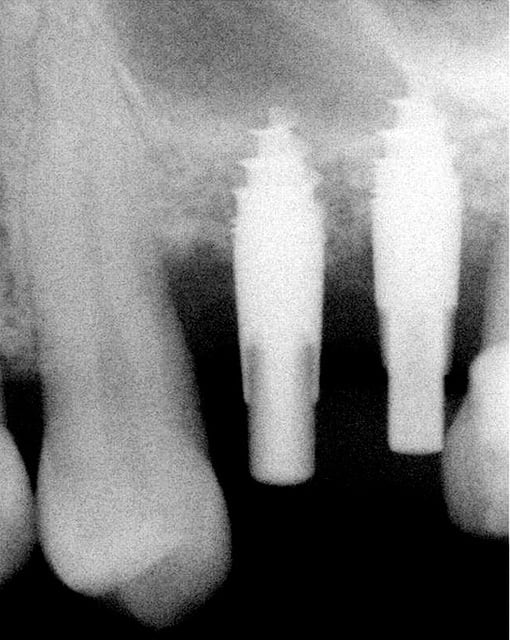

je voulais parler de ce fact pour les implants courts:minimum 4mm os vertical peut suffire (pour eviter un sinus lift externe de tatum) . dans ma pratique depuis quelques années je vois que ca marche , quelques cas cliniques des années passées.

j´ai oublié : 4mm plus 2mm( gagnés par un sinus lift interne)